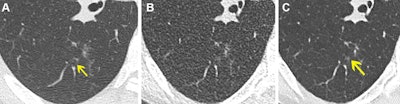

Axial noncontrast chest CT lung window images in a 61-year-old female participant. (A) Normal-dose CT, (B) ultralow-dose CT (ULDCT), and (C) denoised ULDCT show focal ground-glass opacity (yellow arrow). Ground-glass opacity was correctly identified with both normal-dose CT and denoised ULDCT, but it was missed by both readers at ULDCT due to decreased signal-to-noise ratio. Images and caption courtesy of the RSNA.

- The deep-learning algorithm significantly improved the image quality and clarity of the ultralow-dose CT scans and reduced false positives.

- Nodules were also more easily identified on the denoised scans.